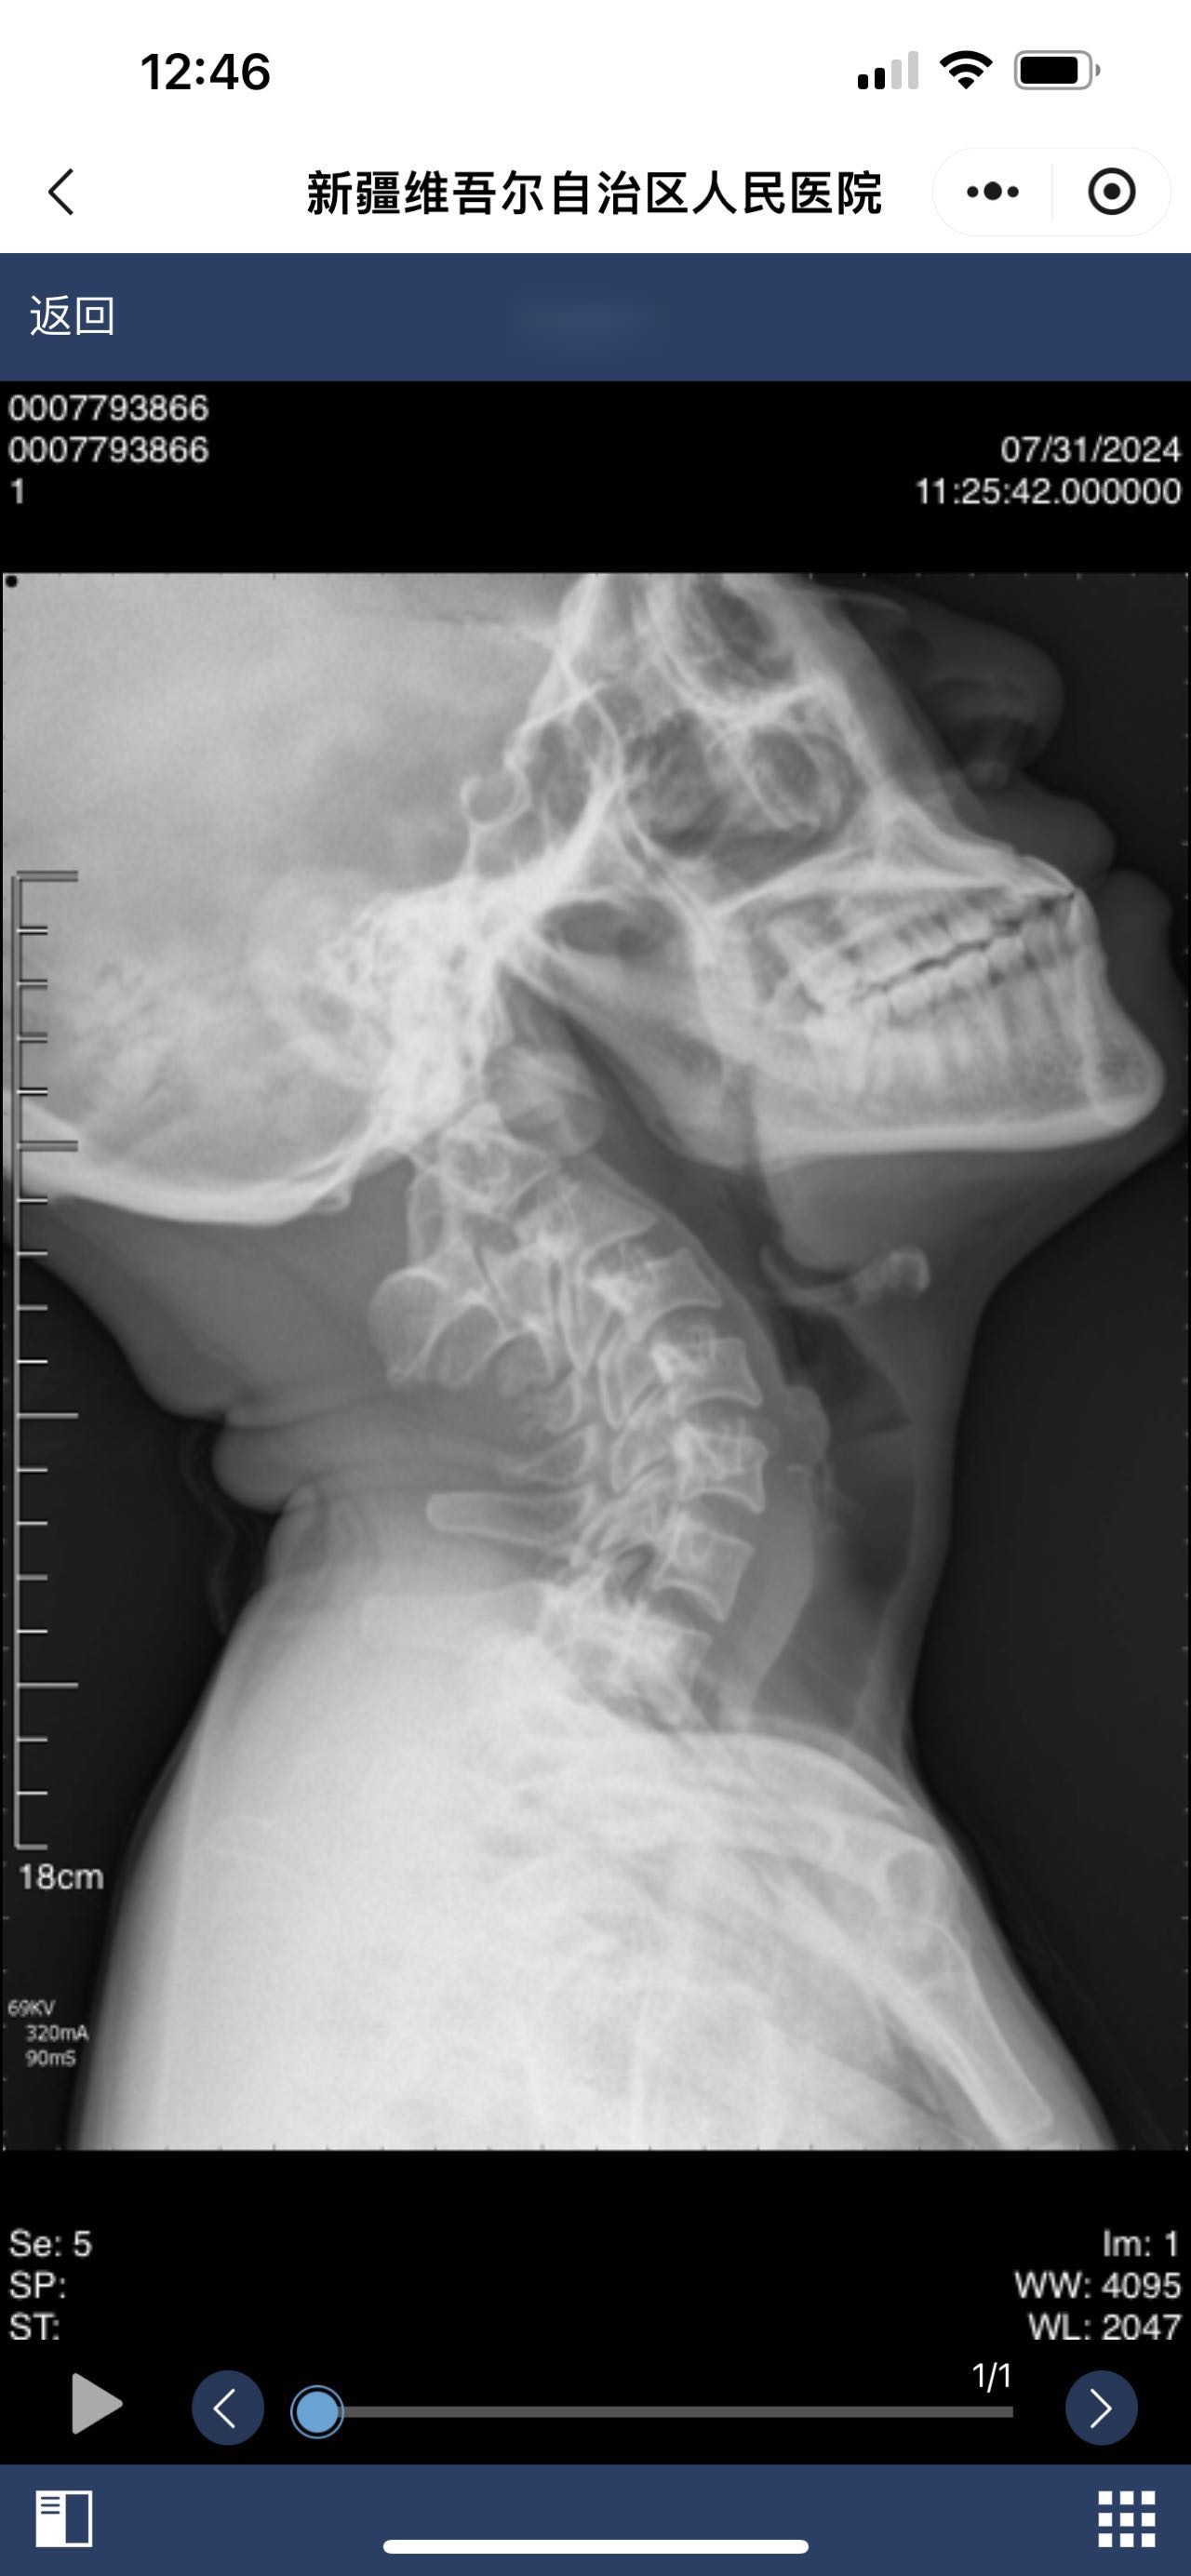

• 诊断:颅底凹陷

• 影像:

• 诊断日期:2024.07.31